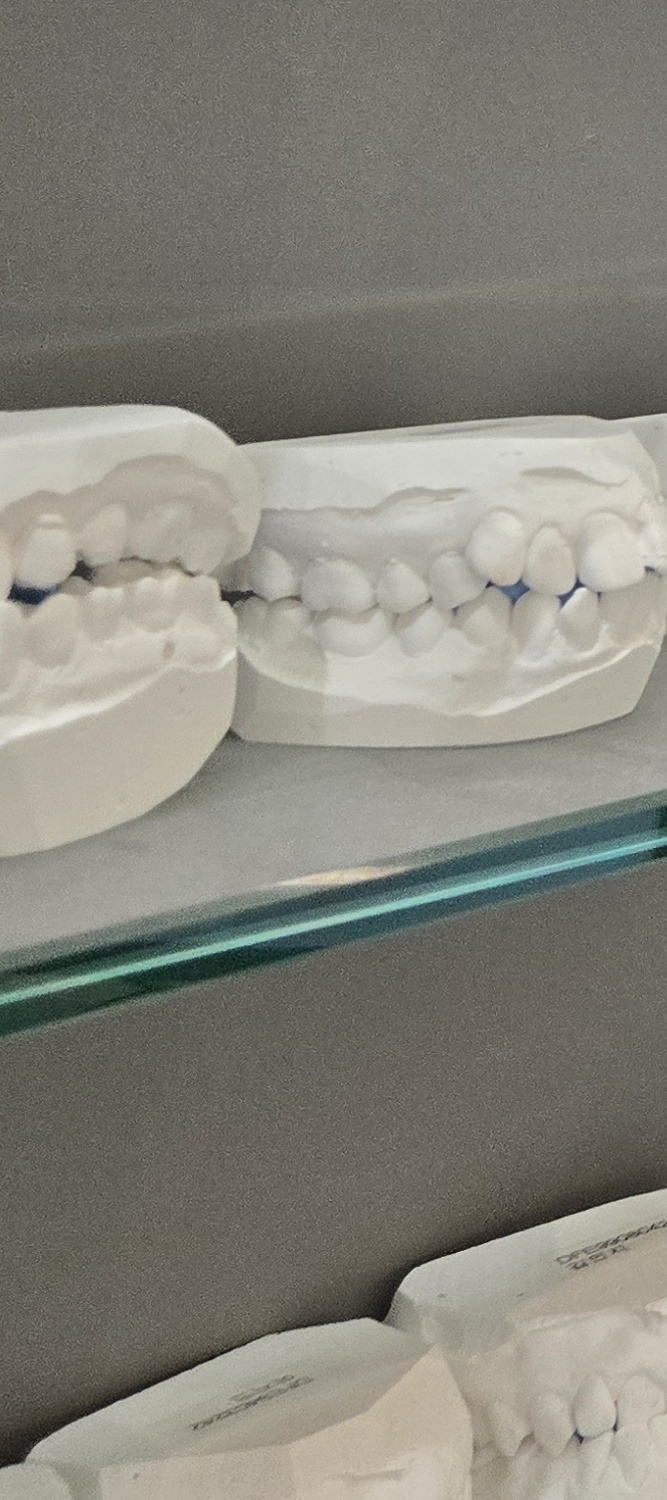

그렇다면 오래된 아말감이나 보철물을 무조건 교체해야 할까 꼭 그렇지는 않으며 현재 상태가 안정적이고, 주변 치아와 잇몸에 문제가 없다면 당장 교체하지 않고 정기적으로 관찰하는 선택도 가능하며 그래서 재치료 계획을 세울 때는 먼저 정확한 진단이 필요하며 겉으로 보이는 상태뿐 아니라, 내부에서 충치가 진행되고 있는지, 치아 구조가 얼마나 남아 있는지, 잇몸과 뼈 상태는 어떤지를 함께 확인해야 하고 이 과정을 통해 단순 교체로 충분한지, 아니면 더 넓은 범위의 치료가 필요한지를 판단하게 될 수 있었어요

오래된 보철물과 아말감은 언제까지 써도 된다는 개념보다는, 정기적으로 점검하면서 사용해야 하는 것에 가까우며 자동차처럼 소모품을 교체하며 관리하듯이, 치아도 시간이 지나면 점검과 보완이 필요하겠고 특히 과거에 치료한 치아일수록 지금의 기준에서 한 번쯤 상태를 확인해 보는 것이 중요할 수 있었어요

결론적으로 오래된 보철물과 아말감의 교체 시점은 문제가 드러났을 때가 아니라, 문제가 커지기 전이 적절한 시점으로 통증이 없을 때 점검하고, 작은 변화가 있을 때 대응하는 것이 치아 수명을 지키는 현실적인 방법이며 오래된 보철물과 아말감을 무조건 불안하게 볼 필요는 없지만 지금 상태를 정확히 알고, 필요한 시점에 필요한 만큼만 치료하는 것, 그것이 오래된 보철물을 현명하게 관리하고 곧 자연치아를 지키는 방법이라 할 수 있어요